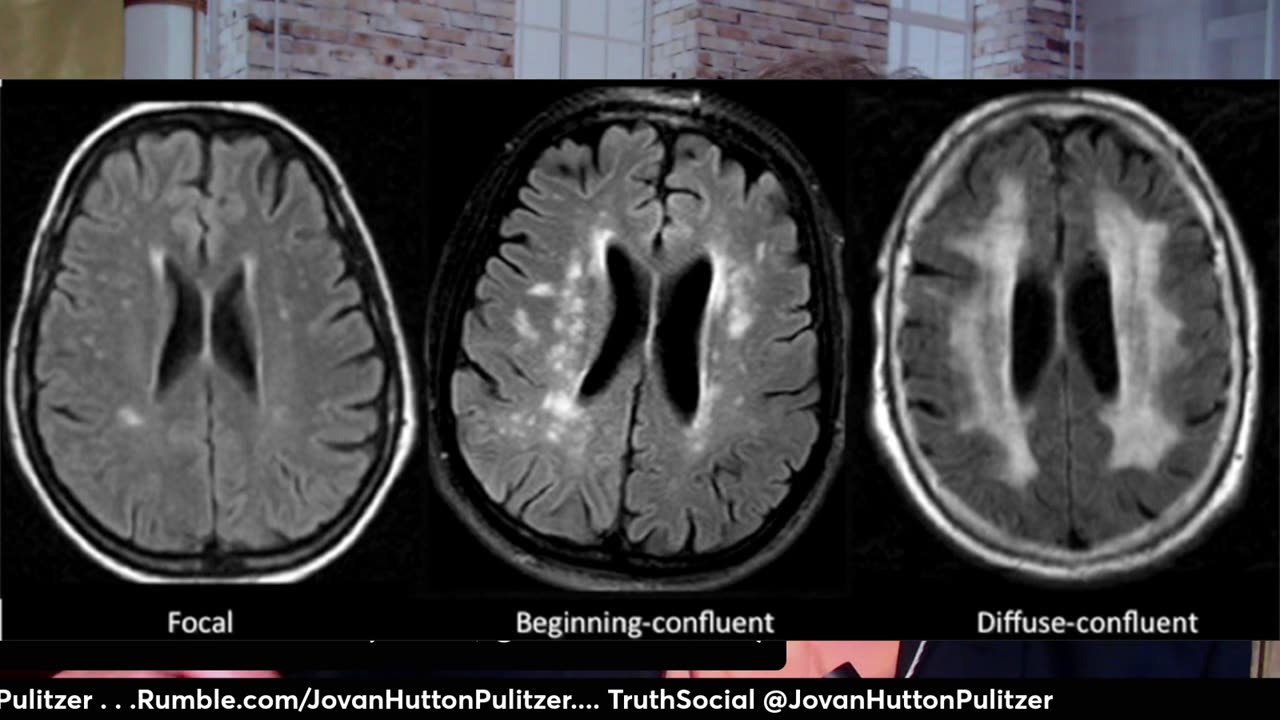

Fazekas 1 что это такое простыми словами 50 фото